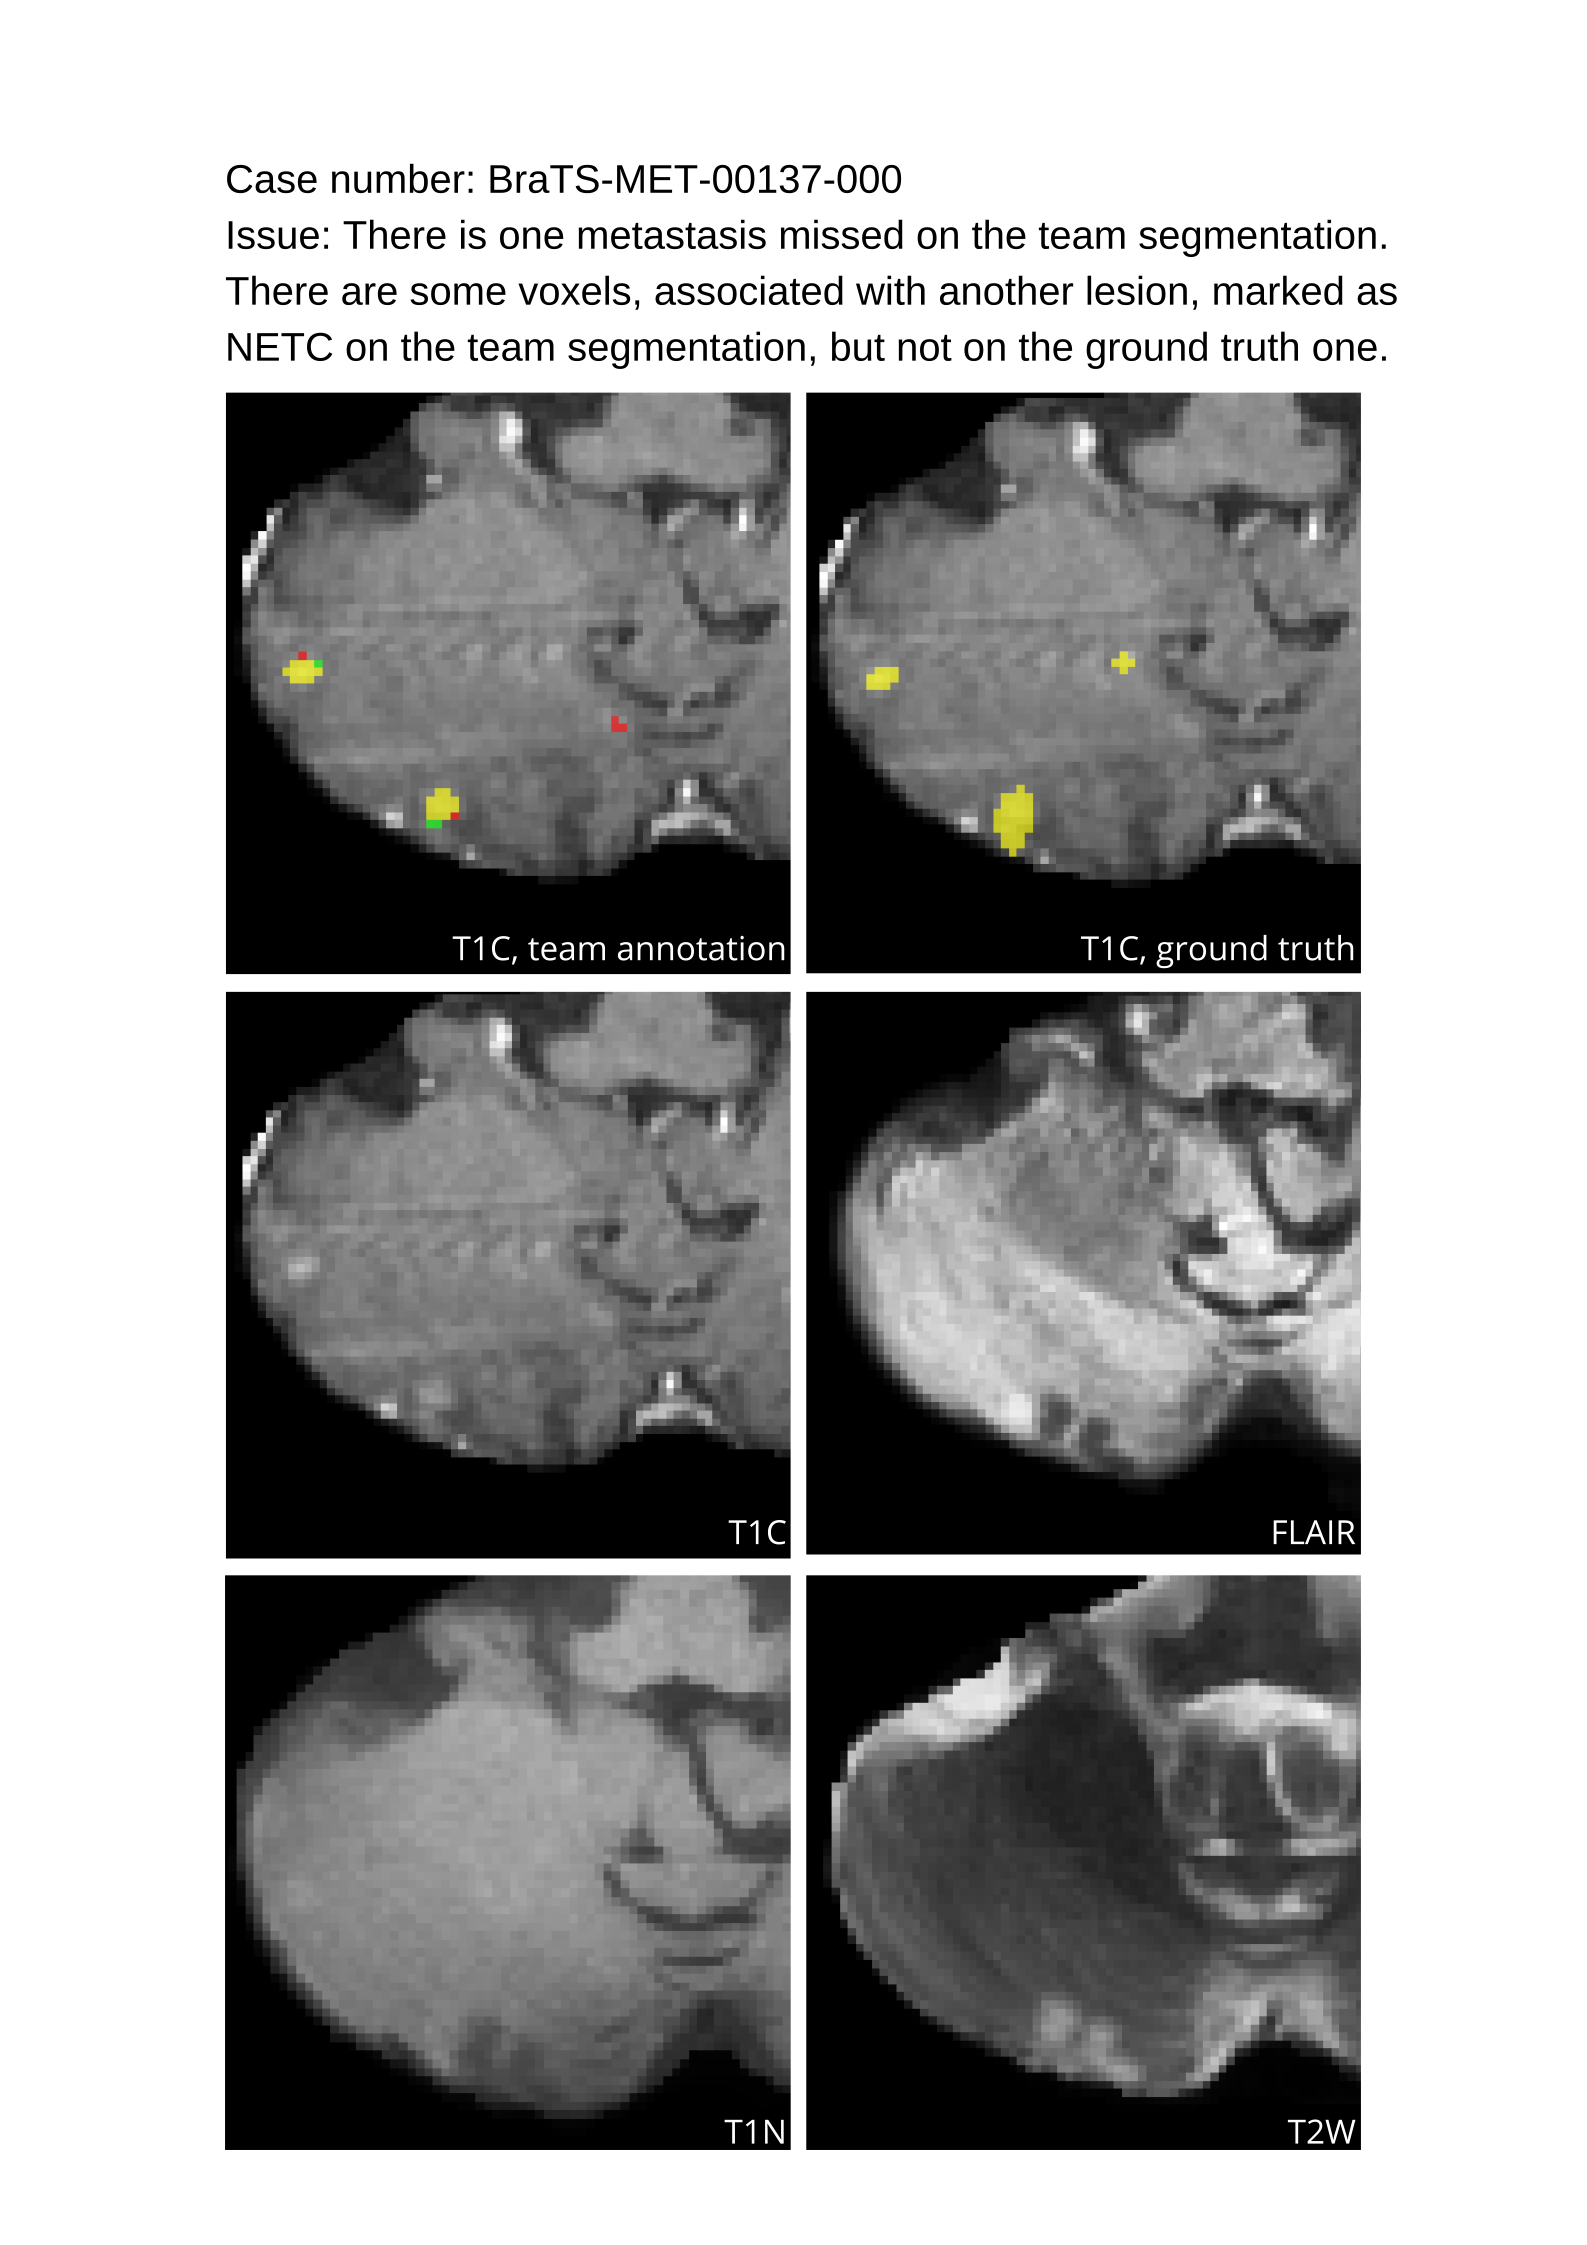

Table 4 provides the relative ranking for each team. Team NVAUTO ranked first in the challenge, with an average rank across subjects of 7.9 and a PatientWise mean of 0.38. Team SY placed second with a PatientWise mean of 0.41 across all patients. The supplementary material depicts the pitfall cases with figures illustrating the false positives or missed lesions.